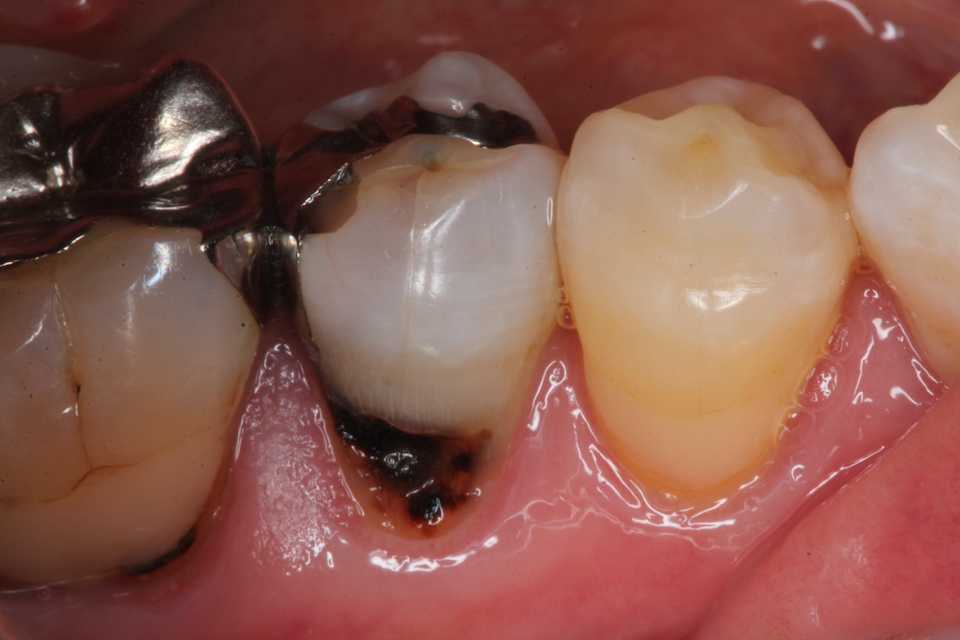

50代女性、左上7、外傷性近心辺縁隆線破折、クラック、自覚症状なし食いしばりの癖がある方で、手前側の6番も補強冠を入れて歯牙破折をなんとか抑えている。この7番も割れて抜歯になる前に補強冠を装着するしかないだろう。とりあえず今日は既存のアマルガムを除去しCRで修復するまで。では時系列でどうぞアマルガムにもクラック(ヒビ)が入っている。クラックα-TCP手前は補強冠、後ろの7番も同じようにするしかないだろう。クラックが深部に進んで離断してしまったら抜歯になる。つづく